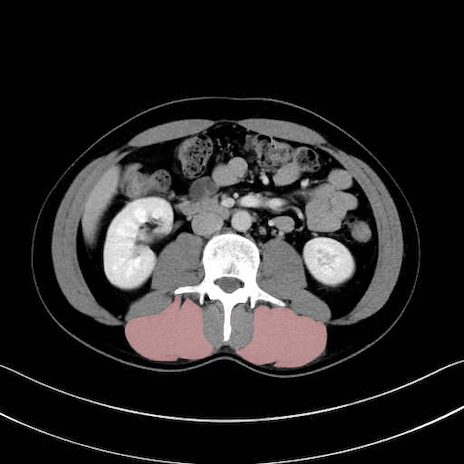

脊柱起立筋(erector spinae)のCT画像の解剖

脊柱起立筋 (Erector spinae)

多裂筋 (Multifidus)